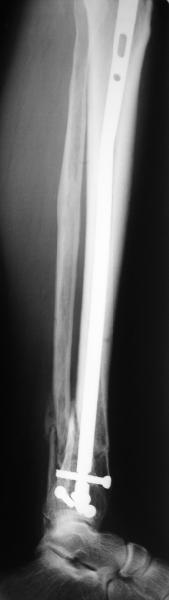

I am just trying to illustrate that prevention of 1)tibial valgus and 2)loss of reduction can be provided without fibular plating. Small changes of conventional nailing techniques allow to maintain reduction of the tibia reliably without adjunctive fibular stabilization.

In delayed cases acute length restoration performed only in the tibia may leave the fibula shortened thus change the mortise. So it is reasonable to restore length of both bones simultaneously by distractor and fix the fibula not with open reduction and plating but just by a single perQ screw. Example attached.